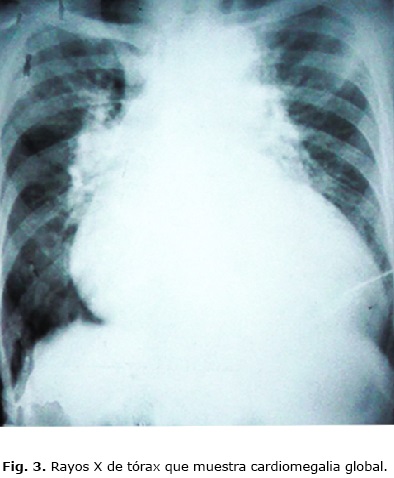

Al examen físico se encontró la tensión arterial en 160/100 mm Hg, signos clínicos de cardiomegalia, edemas periféricos, ingurgitación yugular y hepatomegalia. Se palpaba un thrill sistodiastólico en la muñeca izquierda, donde presentaba una cicatriz. Pudo observarse marcada dilatación y endurecimiento de todas las venas superficiales del plexo braquial de ese lado (Fig. 1, Fig. 2 y Fig. 3).